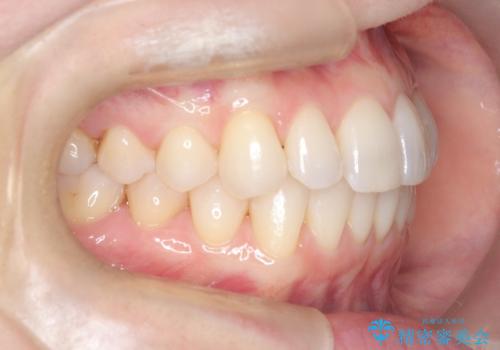

矯正後の後戻りで前歯にガタツキができてしまった インビザラインで改善

- 子どものときにワイヤー矯正をしていたが、後戻りによって前歯のガタツキが気になってきたとのことで来院されました。

アライナー矯正希望だったため、インビザラインによる治療を行いました。

- 7ヶ月